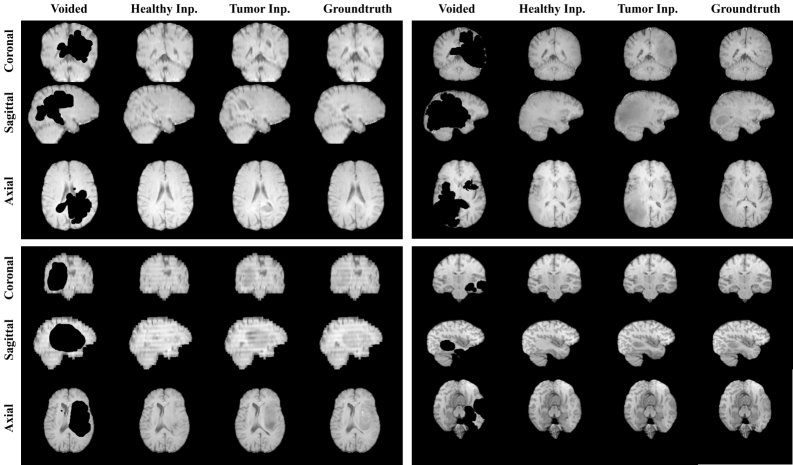

Figure 2: Qualitative inpainting results are presented for four representative subjects across the coronal, sagittal, and axial views. We showcase our ability to reconstruct missing regions in a 3D spatially coherent and anatomically consistent manner, both for tumor reconstruction and healthy tissue, with a single model.

Qualitative Results. The qualitative examples shown in Figure 2 illustrate that the proposed inpainting model is capable of generating anatomically plausible reconstructions, exhibiting spatial coherence across coronal, sagittal, and axial planes. The reconstructed regions generally preserve structural continuity and align well with surrounding anatomical features. However, in certain cases, subtle texture inconsistencies and imperfect transitions between the original and inpainted regions are observable, particularly near region boundaries. These artifacts suggest limitations in the model’s ability to fully harmonize edge details, indicating potential areas for improvement in boundary refinement and texture blending mechanisms.